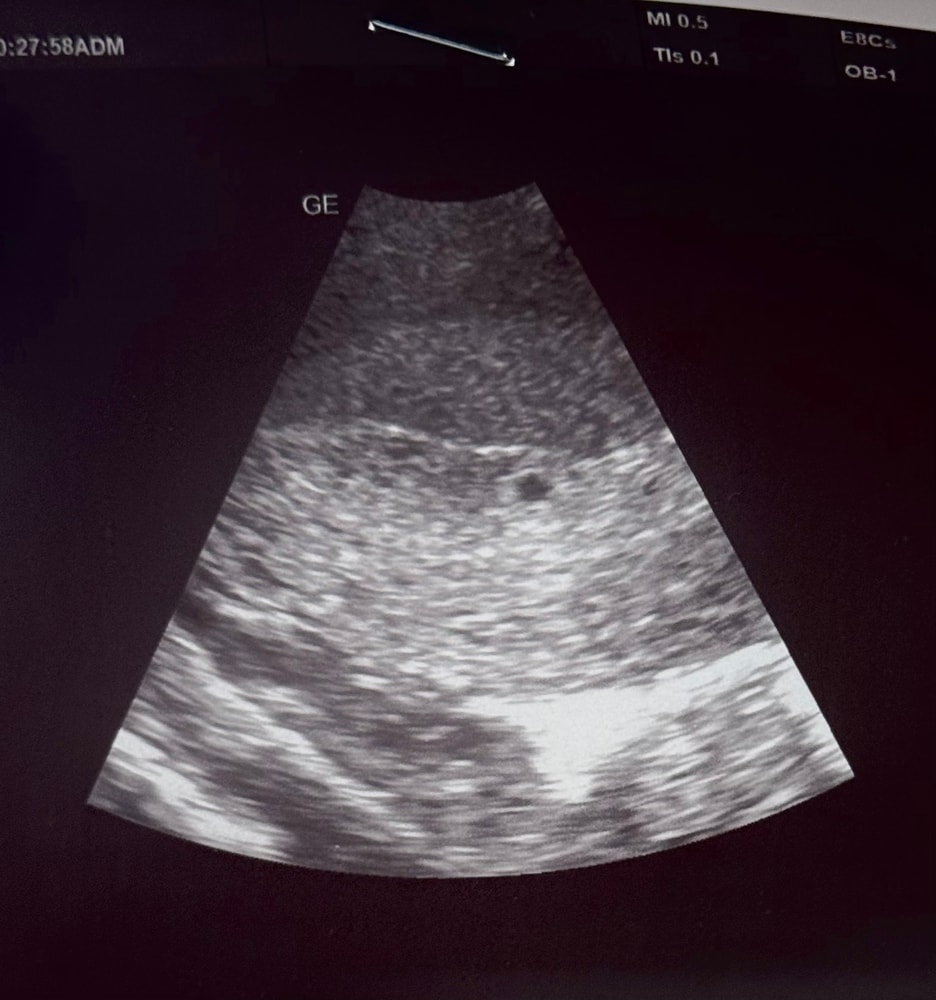

Первое узи 4+5 недель

Сделала узи для спокойствия, что Б в матке - нашли пя 3,2мм сегодня 18дпо, хгч вчера 1211мМЕ теперь жду узи, чтобы увидеть все остальное, очень переживаю и боюсь повторной анэмбриониии( на каком сроке у вас нашли желточный мешочек?